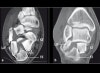

2. CT

CT : 종골 골절(Calcaneal fracture)